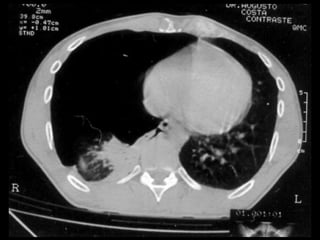

• Diagnóstico – Anamnese –Exame físico – Radiografia de tórax • Inspiração profunda (A) • Expiração profunda – TC de tórax